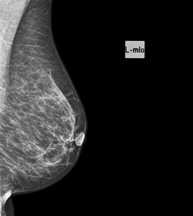

Mamografía digitalizada

La mamografía digitalizada es una técnica innovadora que permite estudiar la mama con una dosis baja de radiación, reduciéndola respecto al empleo de mamografía convencional. La imagen se digitaliza a partir de unos chasis especiales llamados CR. Gracias a estas técnicas de digitalización se obtienen excelentes imágenes, sobre todo en mamas de difícil estudio como las glandulares que se presentan en la mamografía como una mama densa, detectando en este grupo de pacientes mejor las tumoraciones.